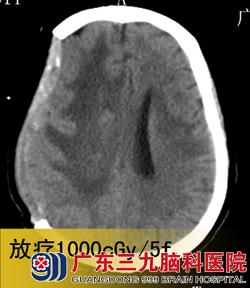

入院3天后,潘女士在广东三九脑科医院接受了“右侧基底节占位性病变取病理活检术+去骨瓣减压术”,术后病理结果为:弥漫大B细胞淋巴瘤。术后第4天,予以抢救性全脑放疗,并同步化疗。2012年11月4日复查头颅CT见右侧基底节病灶明显缩小,中线回位,遂继续予以全脑及局部残留肿瘤放疗。www.999brain.com